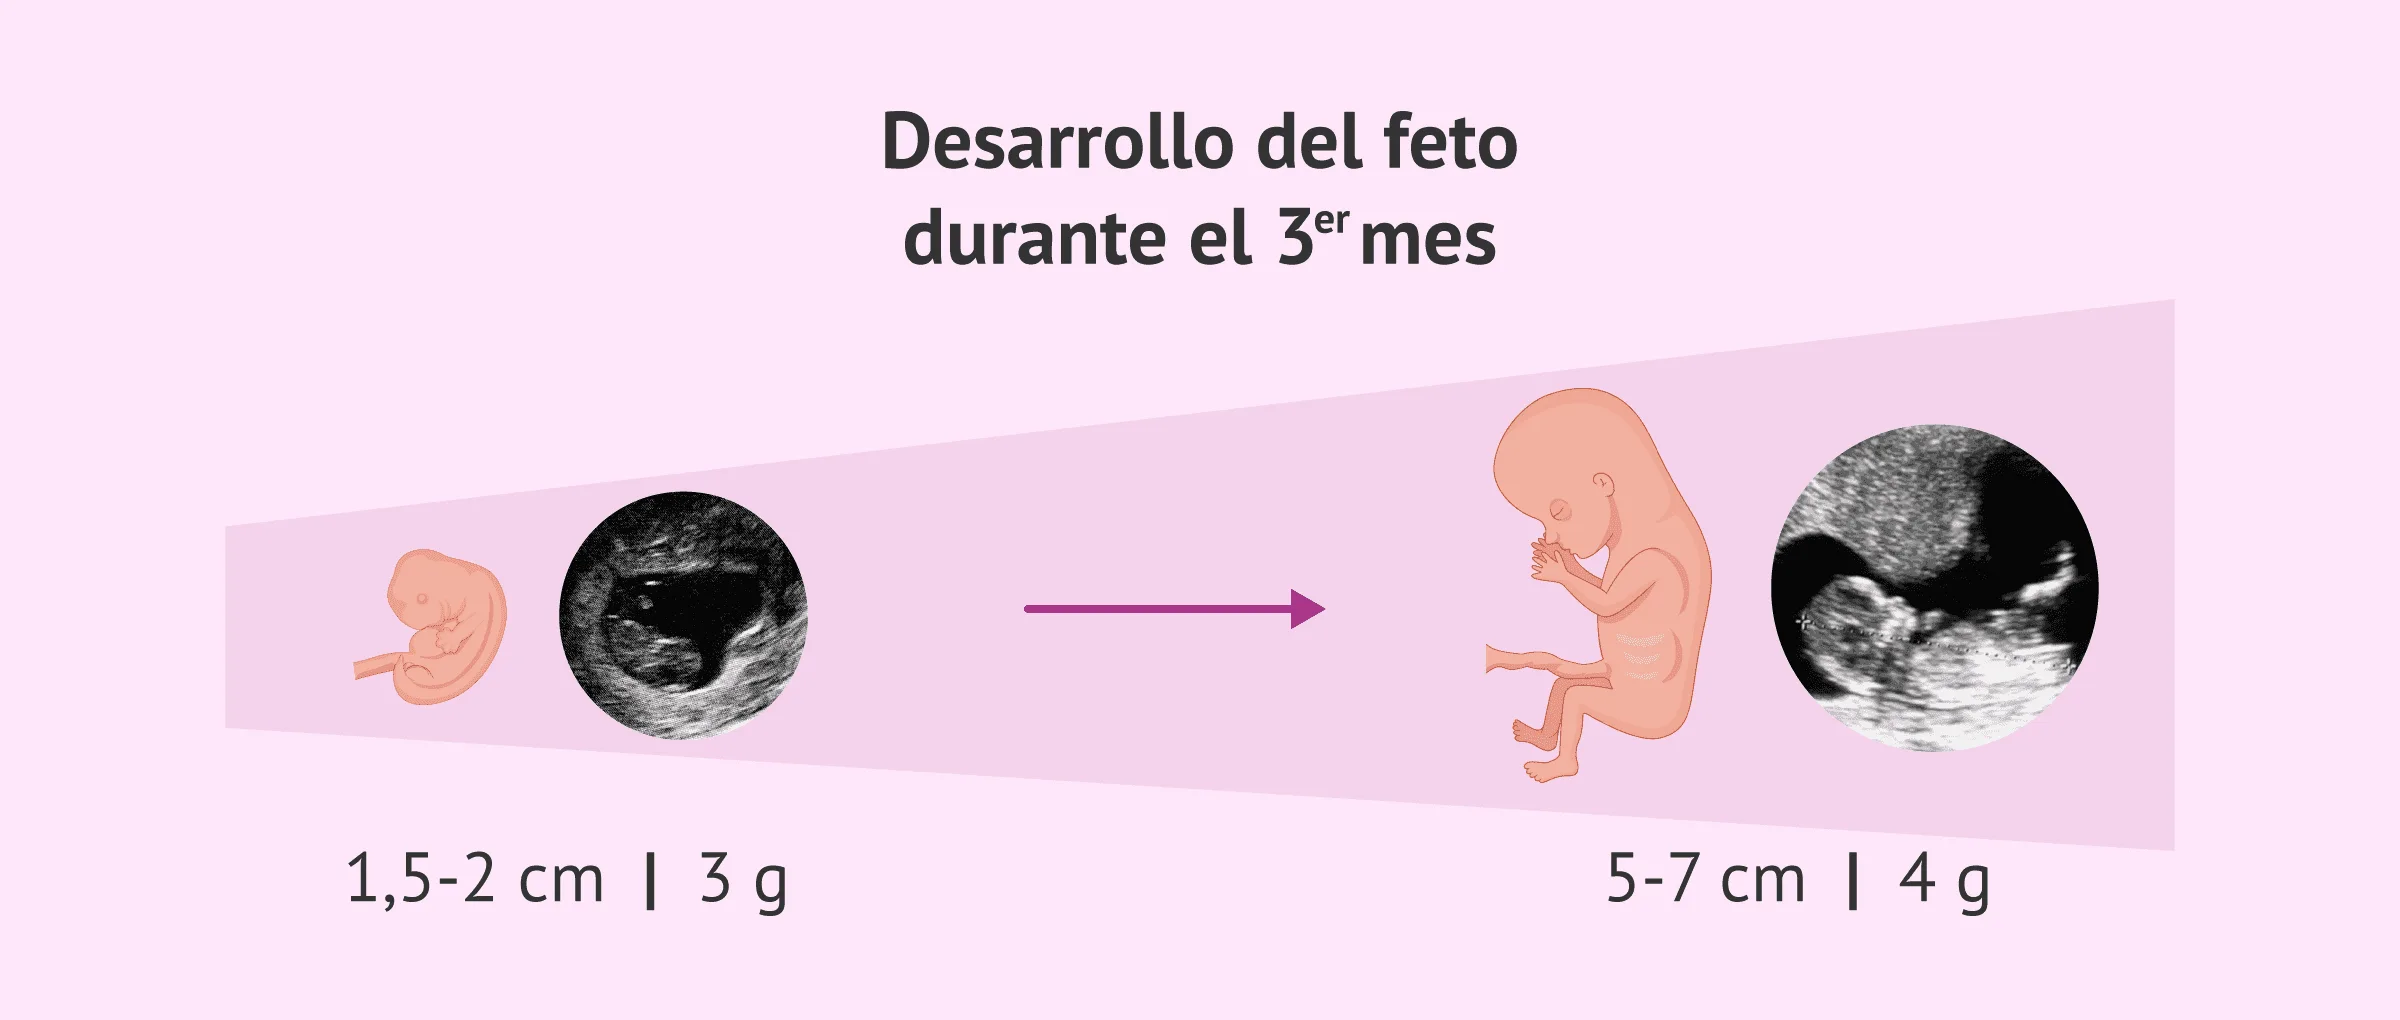

Tercer mes de embarazo desarrollo del feto y sintomas en la mujer

SEMANAS 8 12 DE EMBARAZO 3 MESES SEMANA A SEMANA Baby Suite by Pau